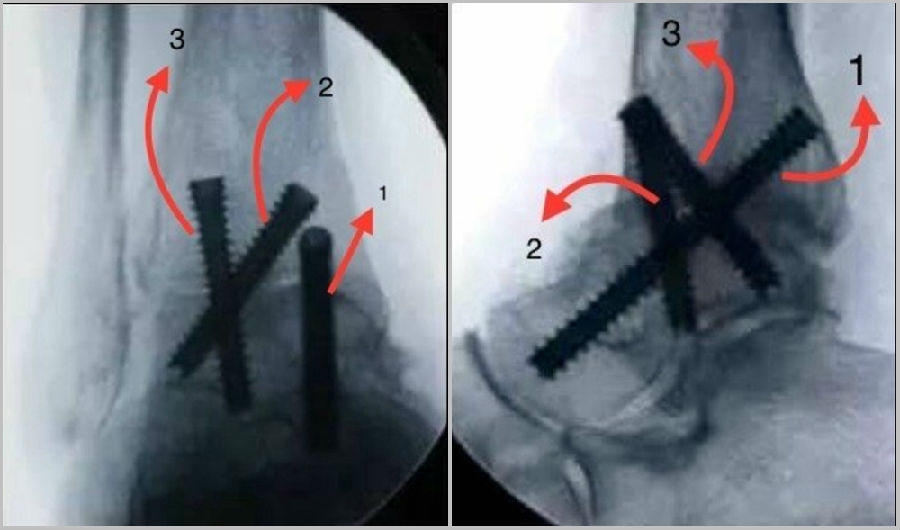

③固定

第1枚螺钉自内踝后侧向前下方向打入距骨头颈部;

第2枚螺钉自前内踝斜向下至距骨体部;

第3枚螺钉自胫骨远端前外侧向距骨体后内侧。

④踝关节融合位置

足位于跖屈和背伸均0°位,外翻5度,外旋5-10度位置。